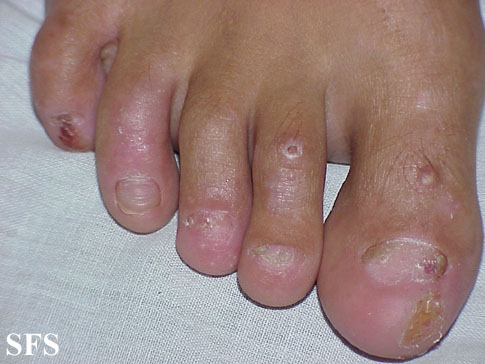

epidermolysis bullosa dystrofic dominant